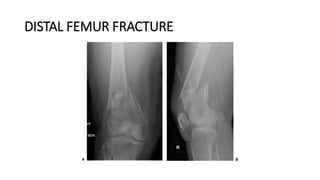

DISTAL FEMUR FRACTURE

DEFINITION

• Fractures of the thighbone that occur just above the knee joint are called

distal femur fractures. The distal femur is where the bone flares out like an

upside-down funnel.

• Distal femur fractures most often occur either in older people whose bones

are weak, or in younger people who have high energy injuries, such as from

a car crash.

• In both the elderly and the young, the breaks may extend into the knee

joint and may shatter the bone into many pieces.

DESCRIPTION

• Distal femur fractures vary. The bone can break straight across (transverse

fracture) or into many pieces (comminuted fracture).

• Sometimes these fractures extend into the knee joint and separate the

surface of the bone into a few (or many) parts. These types of fractures are

called intra-articular. Because they damage the cartilage surface of the

bone, intra-articular fractures can be more difficult to treat.

(Left) A transverse fracture across the distal femur. (Center) An intra-articular fracture

that extends into the knee joint. (Right) A comminuted fracture that extends into the

knee joint and upwards into the femoral shaft